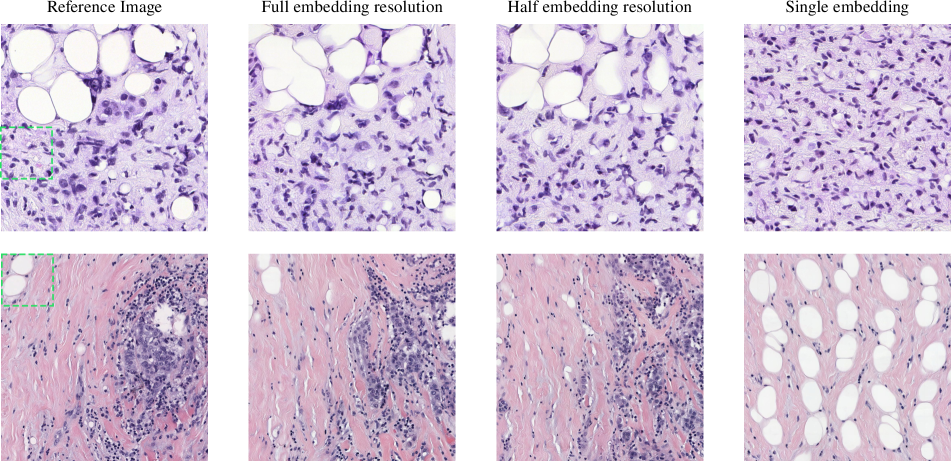

16 Embedding resolution

In Fig. 10 we show synthetic large images, using different embedding granularities from a reference image. When utilizing the full embedding resolution, we use the entire 4×4444\times 4 embedding grid to generate a variation of the original image by interpolating to get conditioning at each i,j𝑖𝑗i,j location. At half resolution, we average the embeddings and use a 2×2222\times 2 grid, leading to more repeated textures in the final image. When using a single embedding (patch indicated with a green box) the generated image is equivalent to infinitely tiling the textures from the reference patch.

Refer to caption

Figure 10: Using coarser conditioning results in repeated textures in the generated large image. When using a single embedding the result is equivalent to an infinitely-tiled patch. Images are at 1024×1024102410241024\times 1024 pixels resolution.